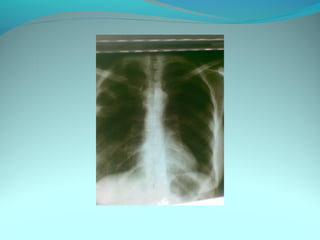

Clarté retroclaviculaire gauche d 3cm de diam

entouré d’une paroi de 1cm d’epaisseur

La limite interne se confend avec le mediastin

Les autre limites sont nette

DIAGNOSTIC

Caverne tuberculeuse gauche